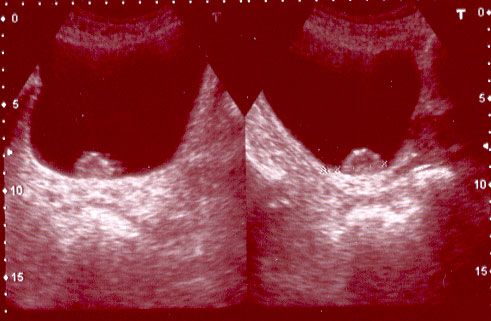

- Ecografía. Es imprescindible su realización en el estudio inicial de una hematuria. Permite valorar eficazmente la cavidad vesical y el resto del abdomen en busca de complicaciones derivadas del tumor y enfermedad metastásica. Detecta con precisión el 95% de los tumores vesicales mayores de 1.5 cm, y un 40% de los más pequeños. En nuestra Unidad de Urología disponemos de ésta ventaja, a fin de realizar un diagnóstico lo más precoz posible.